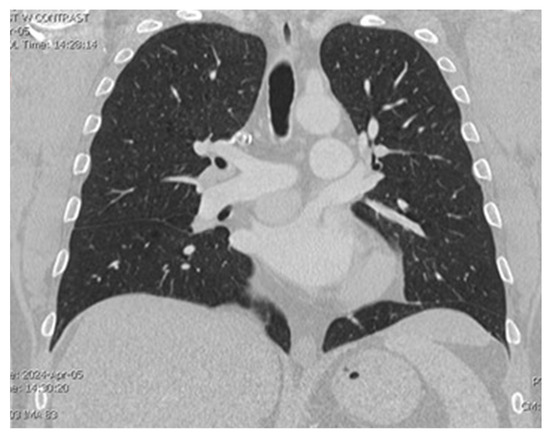

A CT chest scan, now with contrast, was completed on 4/5 and demonstrated a solid mildly enhancing 3.2 cm mass located just superior to the left atrium and just inferior to the right pulmonary artery consistent with findings from the nuclear medicine scan (Figure 1 and Figure 2). There remained a concern for ectopic parathyroid tissue but also a malignant tumor, hence a recommendation was made for tissue sampling. Parathyroid exploration was deferred given that orthotopic parathyroid pathology did not appear to be the source. Thoracic surgery was consulted for possible surgical removal of the gland; however, there was concern about safe accessibility given the location of the gland.

Figure 1. Visualization of the mass located between the pulmonary artery and left atrium on CT chest.